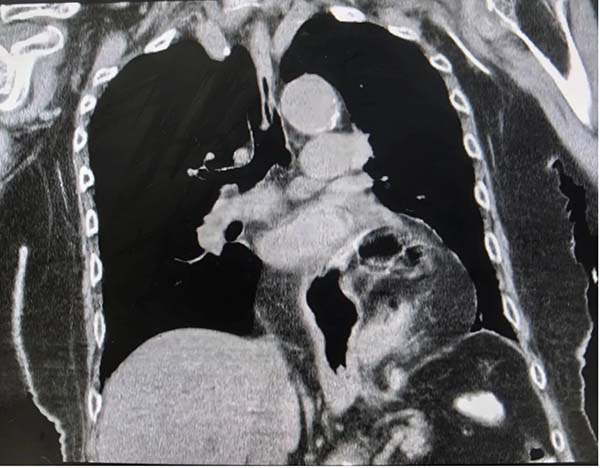

患者相关影像

李老先生因罹患食管裂孔疝,其大部分胃部通过膈肌缺损处突入胸腔,并发生胃扭转,这不仅导致老人无法进食,身体日渐消瘦,更随时有缺血性坏死的风险,病程复杂且凶险。家属带着老人辗转多家医院,均因超高龄、手术风险过高而被告知难以收治。